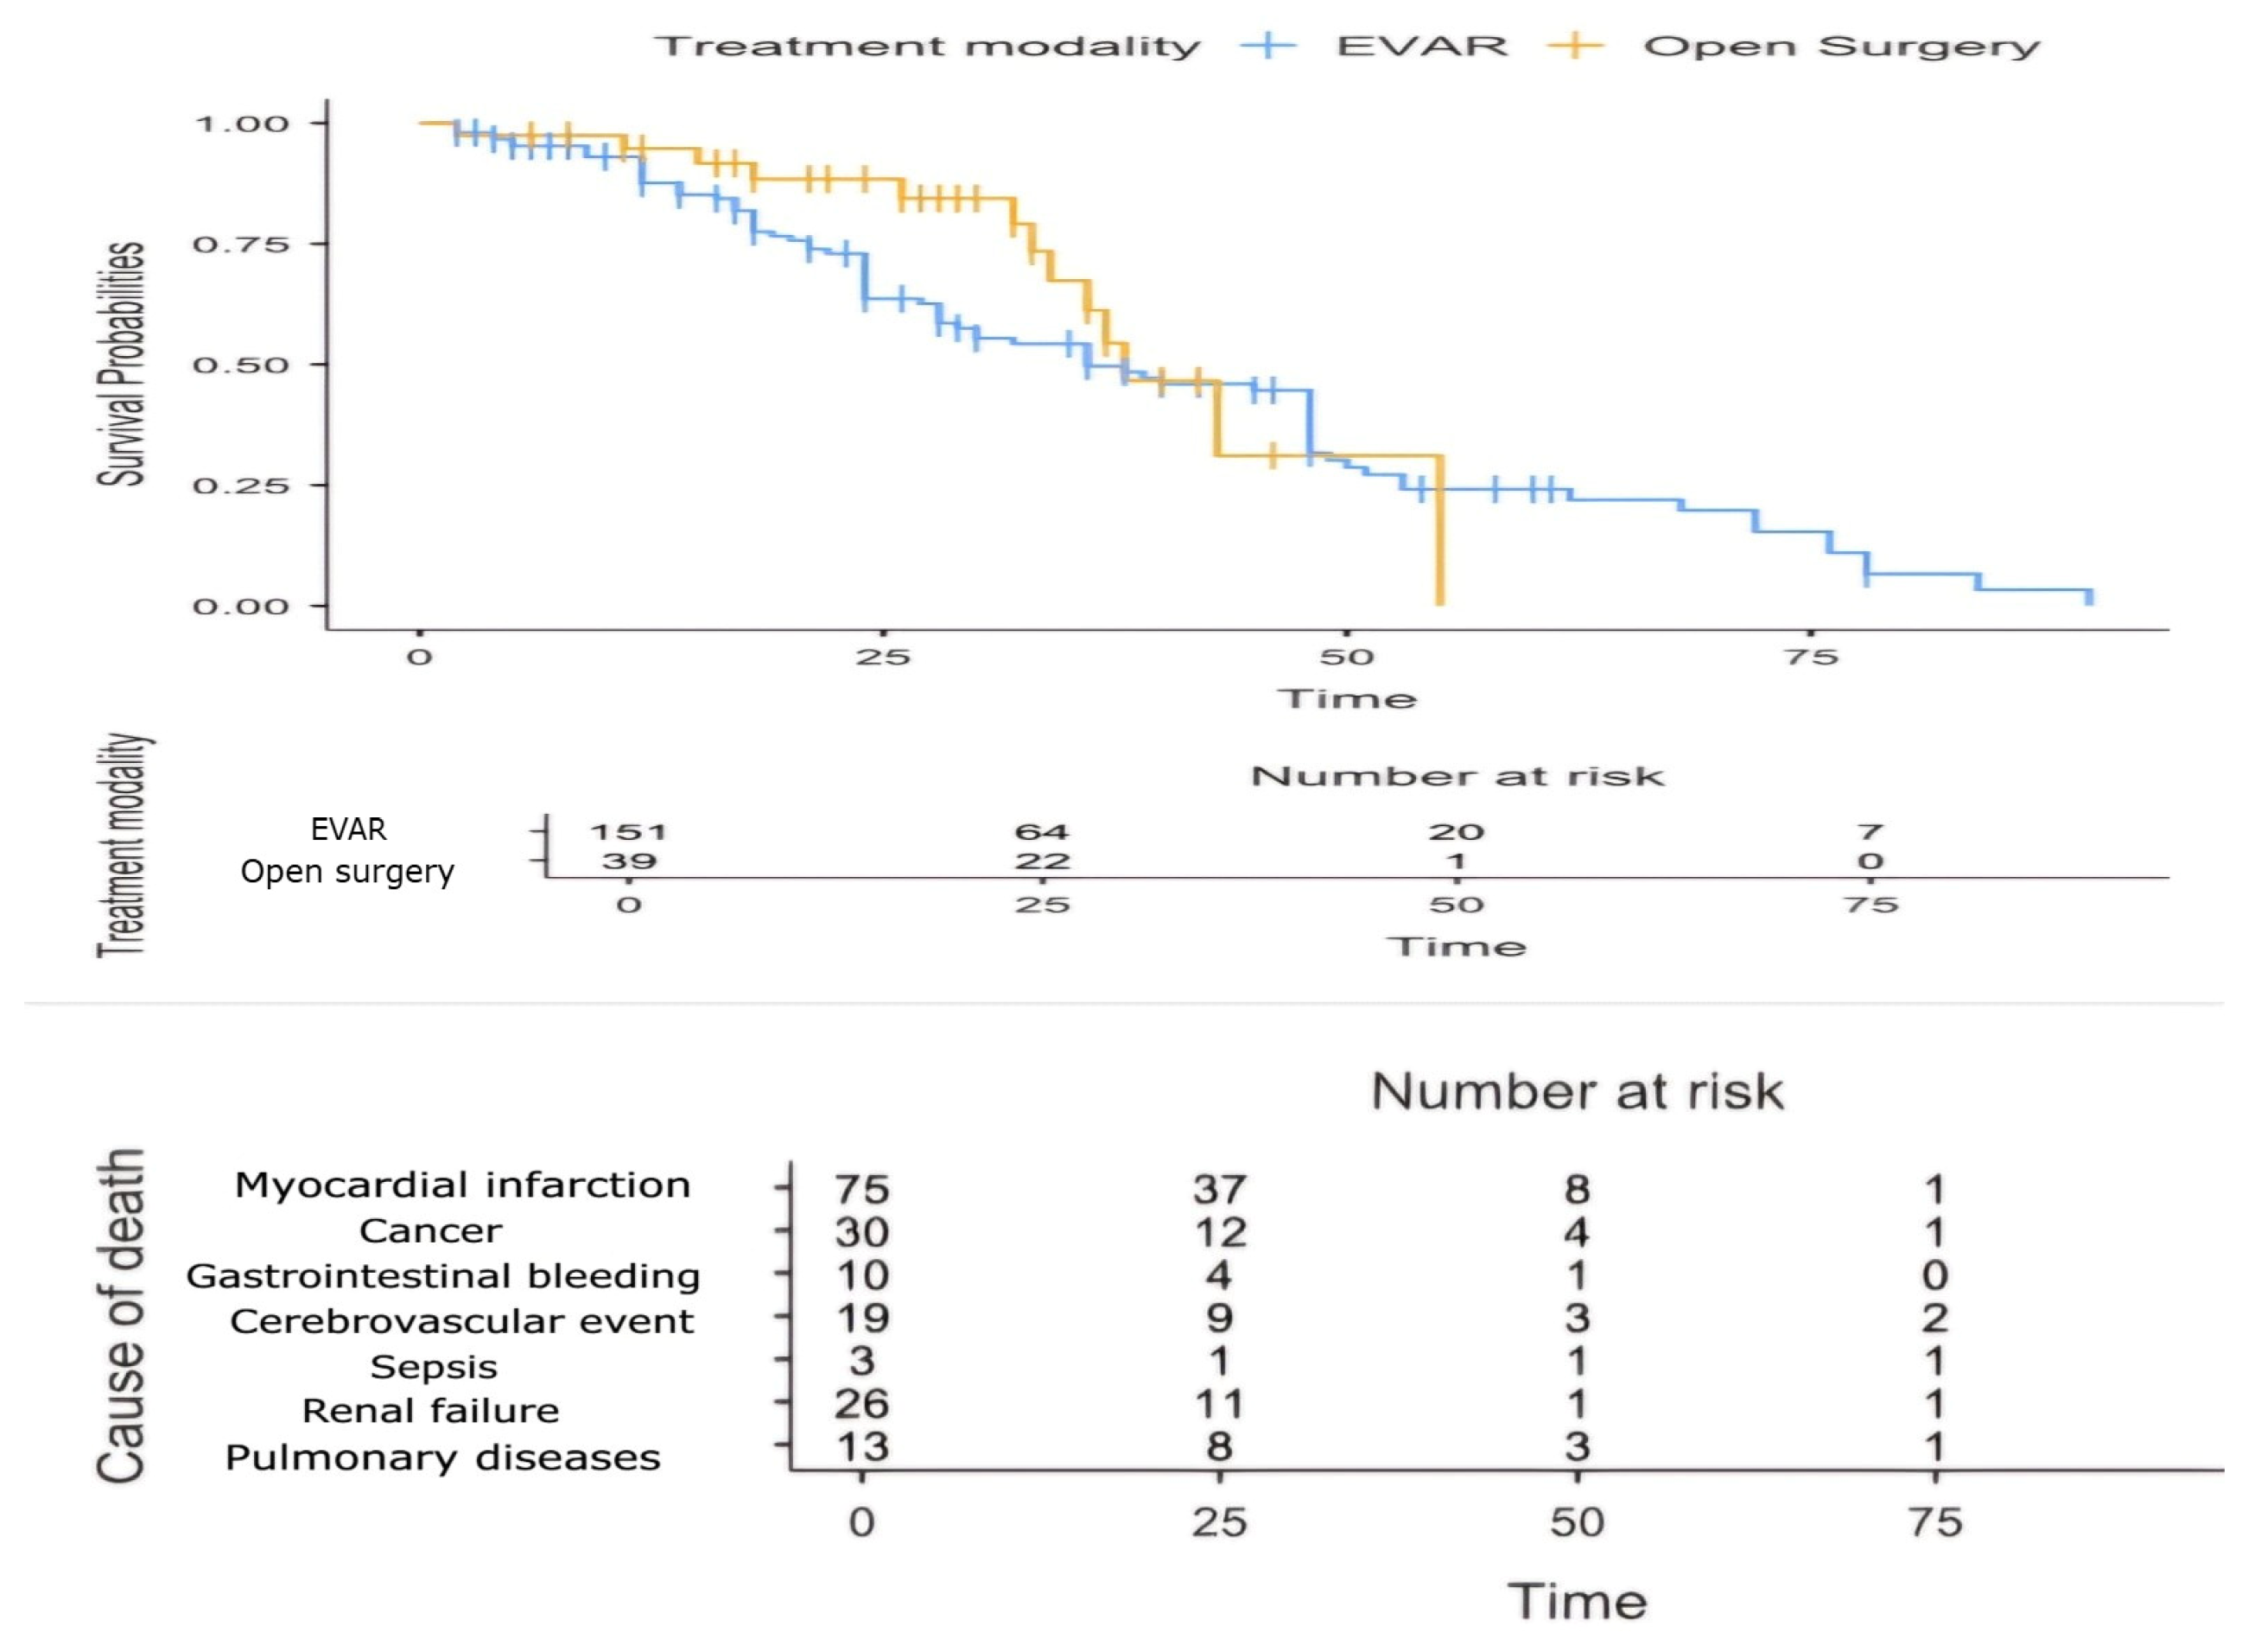

4. Results

5. Discussion with a Brief Review of the Literature